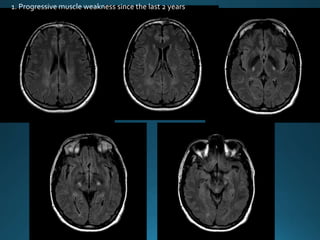

1. Progressive muscle weakness since the last 2 years

Cerebral Autosomal DominantArteriopathy with Subcortical Infarcts and

Leukoencephalopathy (CADASIL) is characterised by recurrent lacunar and

subcortical white matter ischaemic strokes and vascular dementia in young and

middle age patients without known vascular risk factors

autosomal dominant trait

recurrentTIA and dementia

MRI:

widespread confluent white matter hyperintensities . More circumscribed

hyperintense lesions are also seen in the basal ganglia, thalamus and pons

There is relative sparing of the occipital and orbitofrontal subcortical white matter 2,

subcortical U-fibers and cortex